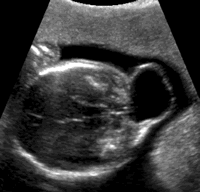

超声诊断胎儿中枢神经系统异常

中枢神经系统畸形种类多、病情复杂且极具破坏性。超声诊断胎儿中枢神经系统异常主要观察侧脑室、丘脑和小脑三个平面,如果三个平面均正常,可以排除95%中枢神经系统的畸形。如侧脑室平面正常,则可排除脑积水、脑萎缩、Dandy Walker畸形、前脑无裂畸形、水脑畸形和胼胝体发育不良;如丘脑平面正常,则可排除脑中线畸形、前脑无裂畸形、视隔发育不良、胼胝体发育不良;如小脑平面正常,则可排除Dandy Walker畸形、脊髓脊膜膨出、后位蛛网膜囊肿、交通性脑积水、Chiari畸形、枕部脑膨出。

脑室扩大(Ventriculomegaly) 通过测量胎儿侧脑室三角区宽度可以诊断脑室扩大。妊娠25周前正常胎儿侧脑室三角区宽度不超过8 mm,妊娠25周后小于10 mm。脑室扩大时,在增大的侧脑室内可以见到脉络丛漂移现象(Dangling)。侧脑室测量时应紧贴脉络丛后缘垂直测量,不要把蛛网膜下腔内壁误认为是侧脑室外侧壁,应该测量远离探头侧的胎儿侧脑室,以消除近探头侧混响伪像的影响 ......